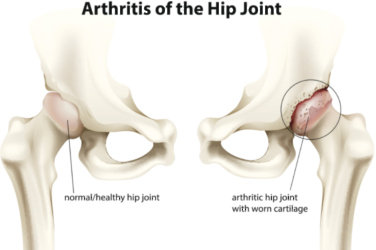

7 ways to treat hip arthritis

Osteoarthritis is a condition that affects the joints, it's the most common form of arthritis in the UK according to the NHS and around 1 million people see there GP about it every year.

What Arthritis Pain Feels Like

Are you wondering if the pain and stiffness in your hips, knees, or fingers are caused by arthritis? Here's how you and your doctor can decide.

Hardly anyone escapes the annoyance of occasional aches and pains, especially as we age. But persistent joint pain and stiffness can be signs of arthritis, which affects about 50 million American adults.

So how do you know if your symptoms are caused by arthritis or something else? While joint pain and stiffness are the most common terms used to describe arthritis pain, the warning signs are pretty specific. Here's what you need to know in order to get the right diagnosis — and the best treatment.

Osteoarthritis (OA) is a common degenerative joint disease and the most common form of arthritis. Knee OA is the most common cause of mobility dependency and diminished quality of life, and obesity is a major contributing factor to the disorder.